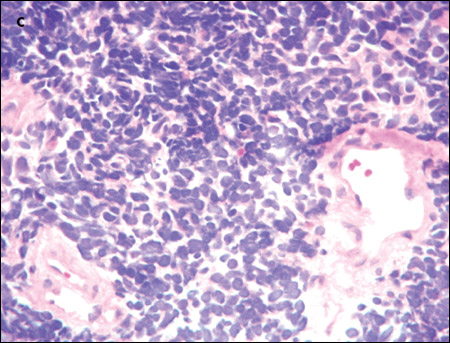

An extensive evaluation of the patient's mass lesions and cytopenias was initiated. He was HIV-positive, but results of tests for hepatitis B and C were negative. Liver function tests revealed the following levels: albumin, 3.1 g/dL; total protein, 5.8 g/dL; direct bilirubin, 0.3 mg/dL; total bilirubin, 1.0 mg/dL; alkaline phosphatase, 175 U/L; alanine aminotransferase, 156 U/L; and aspartate aminotransferase, 92 U/L. Haptoglobin level was 27 mg/dL, and lactate dehydrogenase level was elevated at 1168 U/L. The fibrinogen level was normal at 274 mg/dL, but the D-dimer level was elevated at 602 ng/mL. Results of an enzyme-linked immunosorbent assay for heparin(-induced platelet antibodies were negative. A review of the peripheral smear (C) showed no platelet clumping, schistocytes, or immature cells. Blood and urine cultures showed no bacterial or fungal growth.

Tissue was needed to confirm the diagnosis. The patient received a transfusion of 1 pool of platelets so that a CT-guided liver biopsy could be performed. The results of this biopsy were nonconclusive. However, his platelet count rose dramatically in response to the transfusion—to 150,000/μL.

The patient then underwent a diagnostic bronchoscopy and a biopsy of the lung mass. The lung mass biopsy demonstrated small-cell lung carcinoma; immunohistochemical stains were positive for the neuroendocrine markers AE1/AE3, CAM5.2, cytokeratin 7 (CK7), thyroid transcription factor-1 (TTF-1), synaptophysin, chromogranin A, and CD 56.